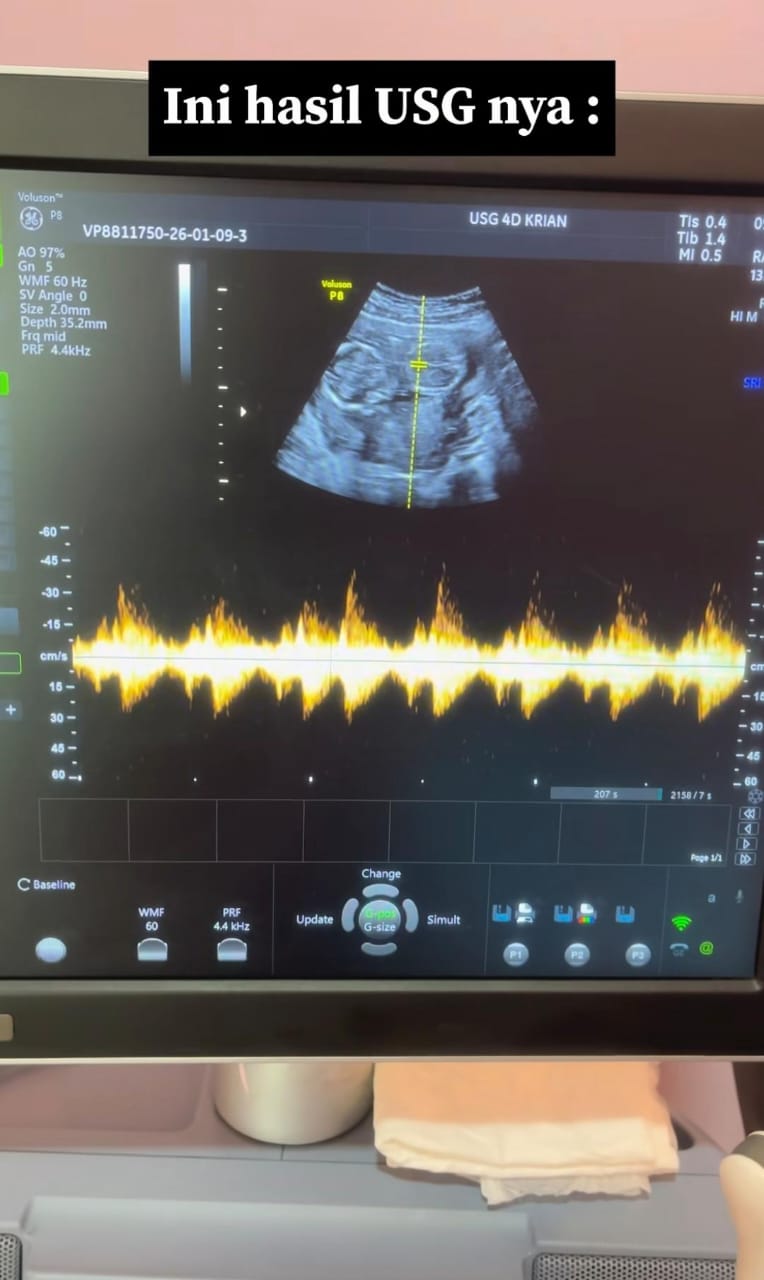

Baru-baru ini, seorang Pakar Obgyn sempat berkongsikan lakonan semula ketika dia mengendalikan sesi pemeriksaan bersama seorang pelajar sekolah menengah. Gadis itu hadir ditemani ibunya dengan keluhan sudah lama tidak didatangi haid. Sudah menjadi prosedur biasa, golongan wanita yang mengalami masalah melibatkan kewanitaan pastinya akan melalui proses imbasan perut.

Sebelum ini, si ibu memaklumkan bahawa gangguan kitaran haid tersebut berkemungkinan berlaku akibat tekanan yang dialami anaknya selepas memulakan sesi persekolahan di sekolah menengah. Namun siapa sangka, hasil imbasan USG mendedahkan kewujudan janin yang telah terbentuk sempurna di dalam rahim remaja itu. Dalam erti kata lain, anaknya disahkan hamil luar nikah.